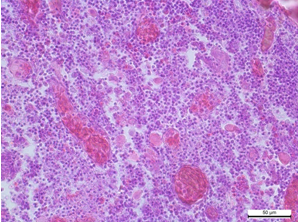

При стафілококової септицемії характерними є некрози та судинні розлади у багатьох паренхіматозних органах, включаючи печінку, селезінку, нирки і легені.

Рис. 3. Печінка. Ареактивне вогнище некрозу гепатоцитів. Гематоксилін та еозин. х 400